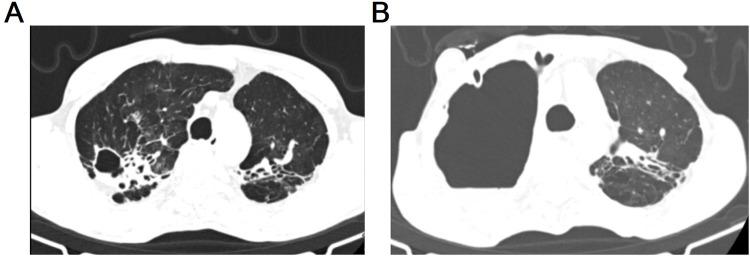

lung disease has gradually become a common clinical condition, with its incidence rate continuously rising, especially among patients with weakened immune function or those with chronic lung diseases. Given the high resistance of to antibiotics, the options for antibiotics are very limited. Additionally, long treatment times and poor patient compliance lead to low cure rates and high recurrence rates, making it one of the significant public health challenges threatening global health. This article presents two cases of patients diagnosed with lung disease using next-generation metagenomic sequencing technology. It reviews and analyzes the current research on along with details from these cases. Furthermore, this article emphasizes the necessity of timely, regular, and comprehensive treatment for lung disease. Meanwhile, we call for the formulation of robust prevention strategies, the optimization and innovation of treatment regimens, and the enhancement of follow-up management after cure to improve the understanding and handling capabilities of lung disease, thereby addressing the increasing clinical challenges.

肺部疾病已逐渐成为一种常见的临床病症,其发病率持续上升,尤其是在免疫功能低下的患者或患有慢性肺部疾病的人群中。鉴于[病原体名称]对抗生素具有高度耐药性,抗生素的选择非常有限。此外,治疗时间长且患者依从性差导致治愈率低、复发率高,使其成为威胁全球健康的重大公共卫生挑战之一。本文介绍了两例使用下一代宏基因组测序技术诊断为[疾病名称]肺部疾病的患者案例。回顾并分析了当前关于[疾病名称]的研究以及这些案例的详细情况。此外,本文强调了对[疾病名称]肺部疾病进行及时、规范和综合治疗的必要性。同时,我们呼吁制定强有力的预防策略,优化和创新治疗方案,并加强治愈后的随访管理,以提高对[疾病名称]肺部疾病的认识和处理能力,从而应对日益增加的临床挑战。